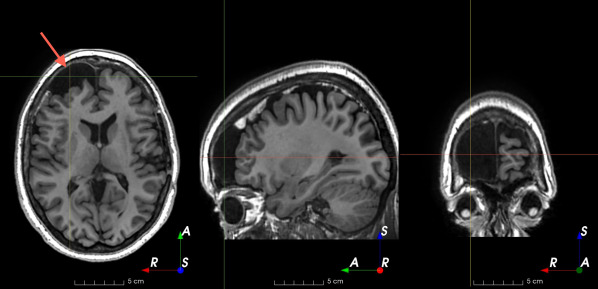

Figure 3: Manual labels from Rater A (green) and Rater D, the model trained with PubFull + EpiPre + Pseudo (magenta). Errors caused by a (a) small resection, (b) blood clot in cavity and (c) brain shift; segmentations corresponding to the (d) 50th, (e) 75th and (f) 100th percentiles giving a DSC of 81.7, 86.5 and 93.8, respectively.

We trained a model using PubFull, EpiPre and Pseudo (2371 images), obtaining a DSC of 81.7 (14.2). Adding the pseudo-labels to PubFull and EpiPre did not significantly improve performance (p=0.176𝑝0.176p=0.176), indicating our semi-supervised learning approach provided no advantage. Predictions from this model are shown in Fig. 3.

Predictions errors are mostly due to 1) resection of size comparable to sulci (Fig. 6a), 2) unanticipated intensities, such as those caused by the presence of blood clots in the cavity (Fig. 6b), 3) brain shift (Fig. 6c) and 4) white matter hypointensities (Fig. 6e). Further work will involve using different internal and external cavity textures, carefully sampling the resection volume, simulating brain shift using biomechanical models, and quantifying epistemic and aleatoric segmentation uncertainty to better assess model performance [24].